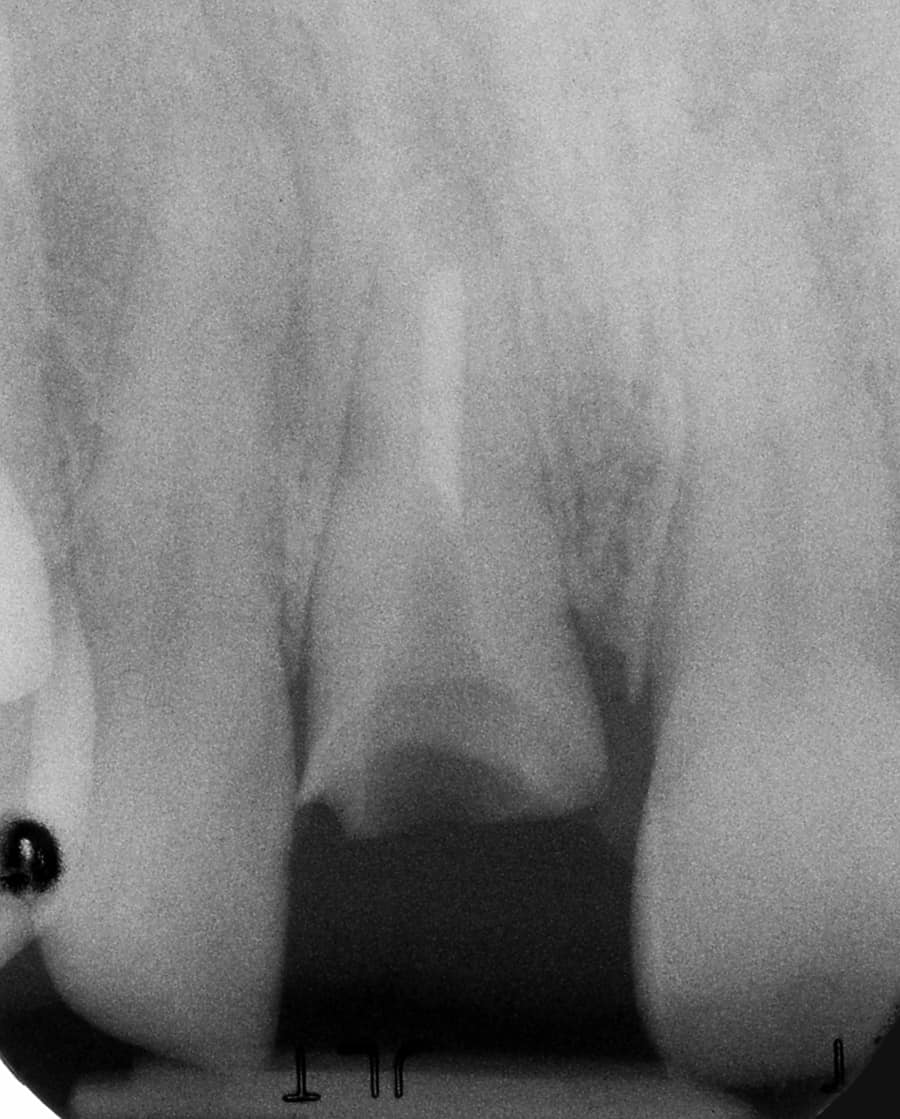

Before:Â Fractured/failed heavily treated upper right central incisor (tooth #8). The root is non-restorable and requires removal. The treatment of choice is a single implant supported restoration.

After: Single, all-ceramic crown attached to an all-ceramic, CAD-CAM designed and generated abutment (implant post). A delayed treatment approach was undertaken: tooth/root removal and grafting; 4 months healing; interim removable partial tooth replacement; implant placement; 6 months healing; proto-type (transitional fixed) implant crown, then the definitive implant restoration. The new tooth blends in perfectly with the natural, adjacent teeth.